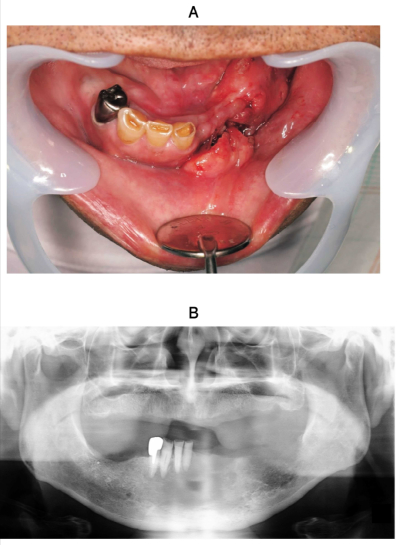

75歳の男性。下顎左側歯肉の異常を主訴として来院した。1か月前から左側下唇に軽度の知覚鈍麻を自覚するようになったという。既往歴として骨粗鬆症、糖尿病および高血圧症がある。初診時の口腔内写真、エックス線写真、CT及び生検時のH-E染色病理組織像を示す。

診断はどれか。1つ選べ。

a. 扁平上皮癌

b. エナメル上皮腫

c. 薬剤関連顎骨壊死

d. 慢性化膿性顎骨骨髄炎

e. びまん性硬化性顎骨骨髄炎